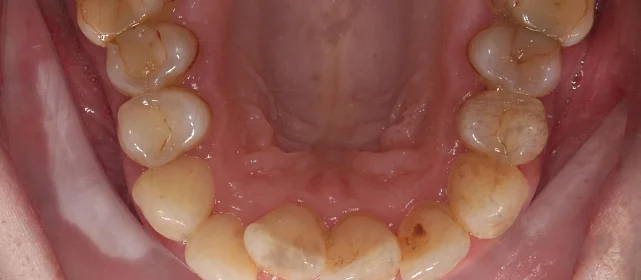

Установка ретейнеров на нижнюю и верхнюю челюсть